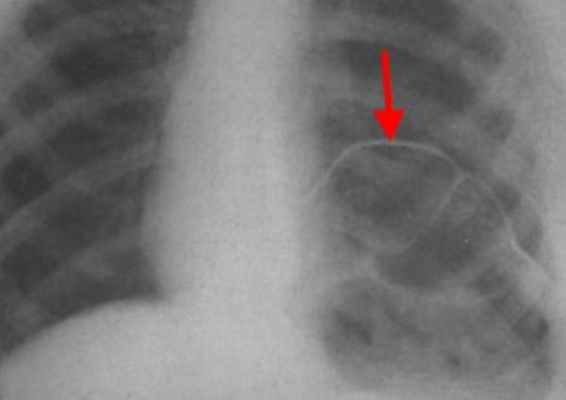

Из физикальных данных большую диагностическую значимость имеют высокое

стояние нижних границ легких с ограничением подвижности, парадоксальное движение диафрагмы при пробе Мюллера. Рентгенологическое исследование органов грудной клетки демонстрирует высокое стояние обоих куполов диафрагмы, наличие субсегментарных ателектазов в базальных отделах легких. Имеет место выраженная гипоксемия: сатурация кислорода в клино- и ортостазе составила соответственно 72% и 96%. При исследовании функции внешнего дыхания определяются значительные нарушения по рестриктивному типу, снижение жизненной емкости легких. Ультразвуковое исследование диафрагмы выявило гиперэхогенность, отсутствие утолщения на вдохе и дыхательной подвижности куполов диафрагмы. Электромиография подтвердило грубую аксонопатию диафрагмального нерва справа и слева.

Рентген. Рентгенологическое исследование является решающим в диагностике релаксации, при этом определяются следующие симптомы:

- стойкое повышение уровня расположения соответствующего купола диафрагмы до 2 – 5 ребра;

- в горизонтальном положении диафрагма и прилежащие к ней органы брюшной полости смещаются кверху;

- контур диафрагмы представляет собой ровную, непрерывную дугообразную линию.

Нередко выявляется ателектаз нижних отделов легкого и смещение средостения.

Релаксация диафрагмы рентген (левый купол)